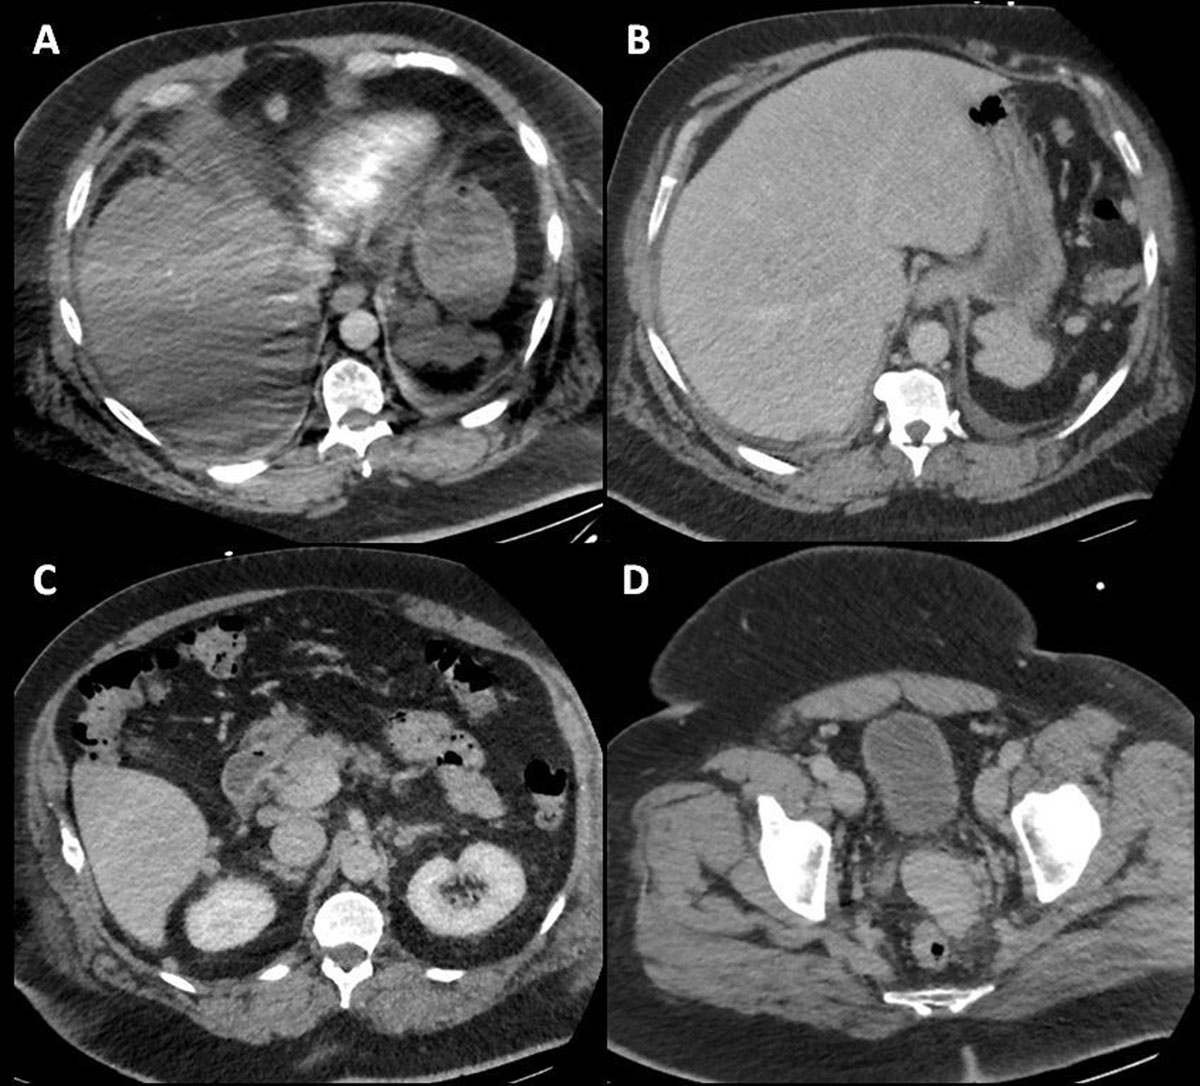

The computed tomography (CT) pulmonary angiography performed to rule out a pulmonary embolism revealed several peritoneal nodules in the upper abdomen (Figure 1A).

CT pulmonary angiography, arterial phase, axial slice (A) shows nodular lesions in the upper abdomen. Abdominal CT, portal venous phase, axial slice (B–D) shows multiples abdominopelvic nodular lesions.

The additional abdominal contrast-enhanced CT revealed multiple other nodules and homogeneous disseminated peritoneal masses (Figure 1B–C1). Splenosis nodules were suspected given the history of splenic trauma and the lack of cancer history. A Tc-99m-tagged heat-damaged red blood cells scintigraphy (Tc99m-DRBC) confirmed the diagnosis of peritoneal splenosis (Figure 2).